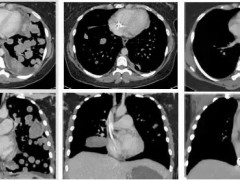

NTRK基因融合阳性突变靶向药恩曲替尼胶囊(罗圣全、Entrectinib、Rozlytrek)让全球首例ETV6-NTRK2融合罕见肺癌重获新生

肺癌2025-12-25